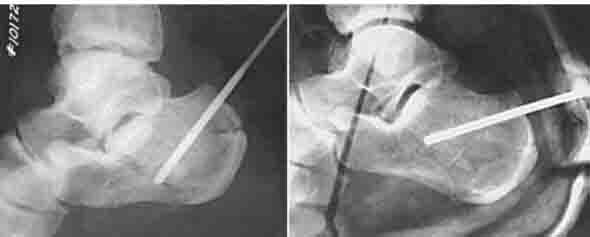

ORIF -единственный способ, позволяющий восстановить конгруэнтность подтаранного сустава, и «при всем богатстве выбора другой альтернативы нет (с)». Вопрос совершенно не в низведении бугра пяточной кости и восстановлении угла Белера – это элементарно делается и аппаратом, и даже еще более простым способом – в бугор в направлении ссади вперед вводится толстая спица, используя ее, как джойстик, бугор низводится, спица проталкивается еще глубже ( картинка из Кэмпбелла). Вот только «проваленную» заднюю суставную поверхность пяточной кости без ORIF and bone grafting не восстановить

И чем вам не нравится ORIF?... Не нашел первоначальный снимок, но очень похож на представленный. Есть только после операции. Через 6 нед. встал и пошел без боли!

IMG_0221.JPG

Точность репозиции суставной поверхности задней фасетки суставной поверхности пяточной кости на представленной вами рентгенограмме вызывает глубокие сомнения, так же как и конечный результат лечения в долгосрочной перспективе. По всей вероятности, у больного был перелом пяточной кости по классификации Sanders типа II A. Часть суставной поверхности задней фасетки, оставшаяся с sustentaculum пяточной кости (короткая линия на вложении, соответствующая субхондральному слоя репонированного фрагмента) находится на месте. А вот большая часть суставной поверхности так и осталась компримирована (длинная линия на вложении, соответствующая субхондральному слою компримированного фрагмента). При репозиции эти две линии должны совпадать. После репозиции, компримированный фрагмент следовало фиксировать к sustentaculum отдельным винтом (не всегда просто точно попасть). Пяточная пластина смещена к пяточному бугру, что не позволило фиксировать к ней самый проблемный участок пяточной кости – суставную поверхность. Не лишней здесь после репозиции была бы и костная пластика.

С уважением, VlaD.